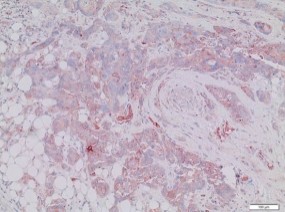

Baccelli, I., Schneeweiss, A., Riethdorf, S., Stenzinger, A., Schillert, A., Vogel, V., Klein, C., Saini, M., Bauerle, T., Wallwiener, M., Holland-Letz, T., Hofner, T., Sprick, M., Scharpff, M., Marme, F., Sinn, H.P., Pantel, K., Weichert, W., & Trumpp, A. (2013). Identification of a population of blood circulating tumor cells from breast cancer patients that initiates metastasis in a xenograft assay. Nature Biotechnology, 31(6), 539-544. doi: 10.1038/nbt.2576